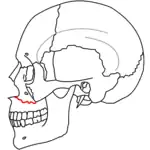

At the beginning of the 20th century, René Le Fort mapped typical locations for facial fractures; these are now known as Le Fort I, II, and III fractures (right).[7] Le Fort I fractures, also called Guérin or horizontal maxillary fractures,[14] involve the maxilla, separating it from the palate.[15] Le Fort II fractures, also called pyramidal fractures of the maxilla,[16] cross the nasal bones and the orbital rim.[15] Le Fort III fractures, also called craniofacial disjunction and transverse facial fractures,[17] cross the front of the maxilla and involve the lacrimal bone, the lamina papyracea, and the orbital floor, and often involve the ethmoid bone,[15] are the most serious.[18] Le Fort fractures, which account for 10–20% of facial fractures, are often associated with other serious injuries.[15] Le Fort made his classifications based on work with cadaver skulls, and the classification system has been criticized as imprecise and simplistic since most midface fractures involve a combination of Le Fort fractures.[15] Although most facial fractures do not follow the patterns described by Le Fort precisely, the system is still used to categorize injuries.[5]

| Le Fort I fractures | |